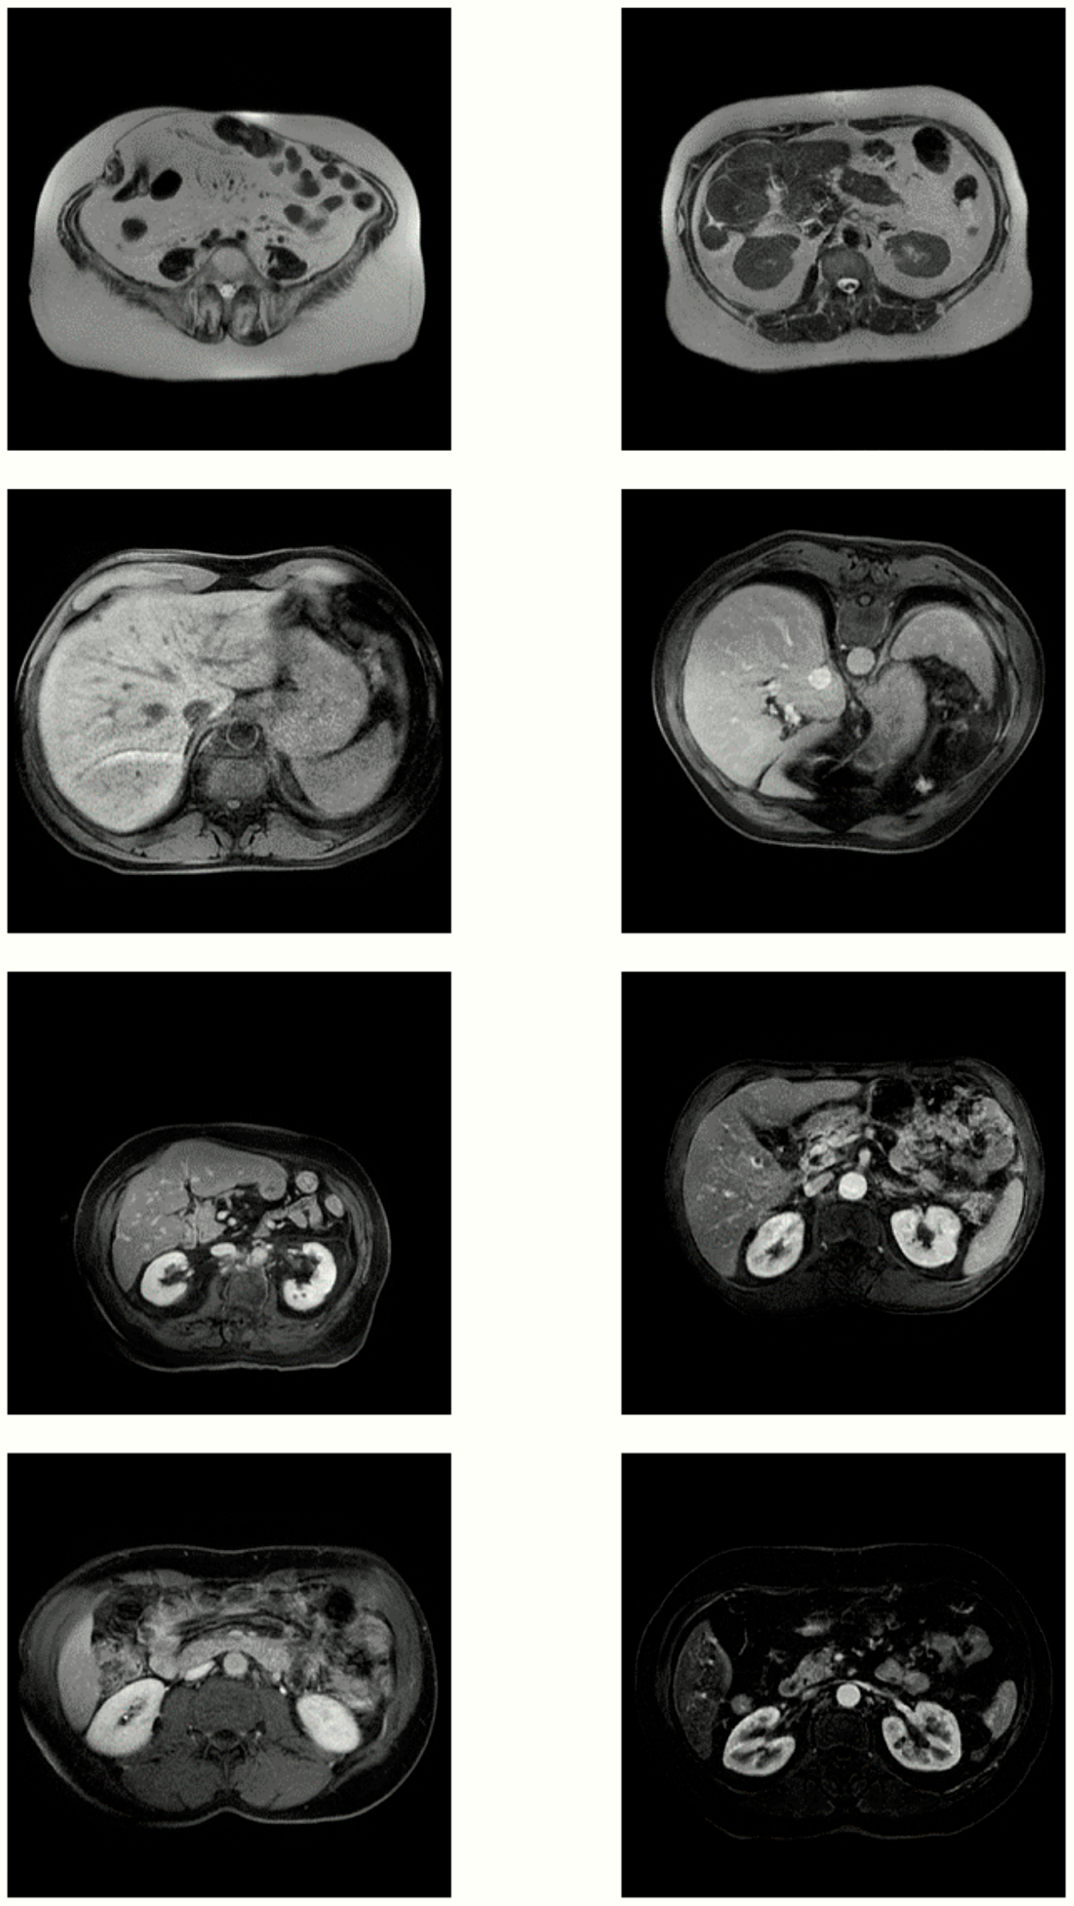

3.2. Visual Inspection

1.1. Data Augmentation